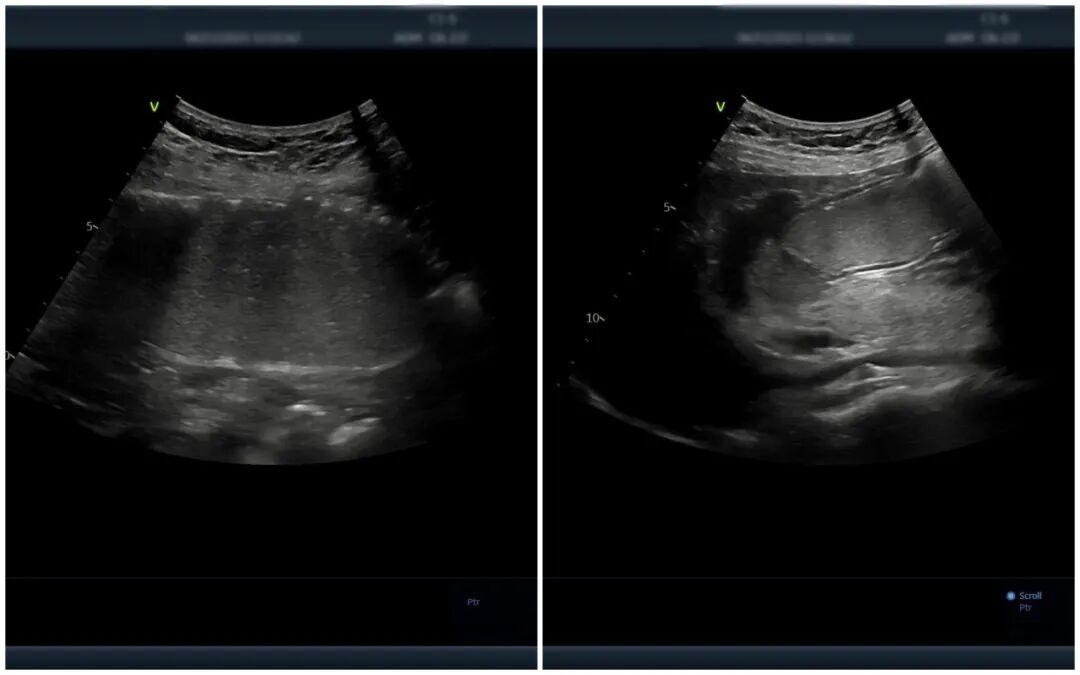

简单来说,就是患者在空腹8小时后,喝下一杯香甜顺滑、形似“糊糊”的胃肠超声造影剂,以此充盈胃腔和十二指肠,有效排除胃肠道内的气体,形成优良的“透声窗”。随后,超声医师通过超声设备,可清晰观察到胃壁和肠壁的层次结构、厚度变化、蠕动状态以及周围毗邻脏器的情况,就像给胃肠道做了一次“B超”,轻松便捷。

△胃肠超声造影提示:黏膜层毛糙,回声减低,胃壁呈局限性增厚,符合慢性胃炎声像图特征